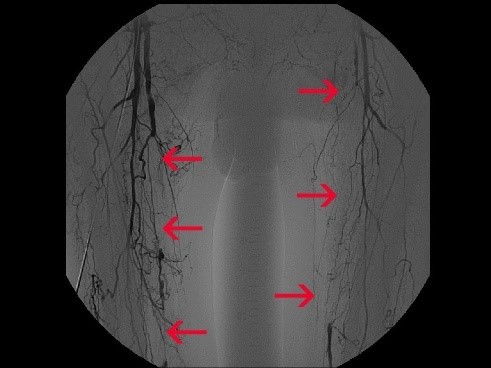

Um die Möglichkeiten der Anlage einer Fistel besser beurteilen zu können, den Einsatz von Fremdmaterial zu begrenzen und letztlich eine lange Offenheit des Dialysezuganges zu gewährleisten, erfolgt zur Planung der Eingriffe neben der Duplexsonographie der Arterien und Venen (Ultraschallgefäßdiagnostik) regelmäßig eine Kohlendioxidphlebographie (Röntgendarstellung der Gefäße ohne Kontrastmittel). Das auch als "CO2-Mapping" bezeichnete Verfahren ermöglicht die Erstellung einer "Gefäßlandkarte", um den am besten geeigneten Venenabschnitt zu finden.